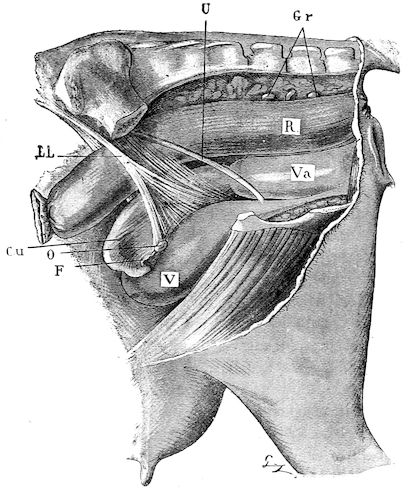

Fig. 1.—Rachitis in a young goat.

Rachitis is a disease of youth, and is common both to the human species and to all domestic animals. It is characterised by irregularities in development and by imperfect consolidation of the bones. The boundary between rachitis and osseous cachexia is difficult to define and in fact at the present moment the two diseases can scarcely be defined with exactitude. Rachitis again is often complicated with softening of the bones, disease of the limbs, arrested development, etc., but it must not be forgotten that although the irregularities in ossification and development of the skeleton are the symptoms most striking to the eye, they do not stand alone, and that from the point of view of development all the tissues, including the muscles, are more or less affected and that most of the physiological functions such as digestion and the secretion of urine are deranged.

Symptoms. The onset is absolutely insidious and the diagnosis of rachitis is never made until nutrition has long been abnormal.

This disturbance of nutrition is revealed by irregularity and abnormality in appetite, by difficulty in rising and moving about, and by the animals lying down for long periods. The subjects are feeble, sluggish and badly developed.

Next supervenes the second phase characterised by deformity of bones. This is of two kinds—deformity in the neighbourhood of joints (deformity or enlargement of the epiphyses) and deformity of the diaphyses. The former results from irregularity in ossification of the articular cartilages. The latter is followed by loss of rigidity in the bones of the limbs which, under the influence of the body weight and of muscular contraction, bend in different directions.

The bones appear of increased thickness principally towards the 6articulations. The latter are deformed, and on palpation are found to be surrounded by uneven and irregular growths.

The front limbs are distorted. In young pigs, lambs, and less frequently in foals, calves and dogs, the jaws become deformed, and mastication is rendered difficult.

The vertebral column may also be affected, and lordosis (bending downwards of the back) or skoliosis (lateral bending of the back) is somewhat frequent.

Cyphosis, or upward bending of the back, seldom occurs, and when seen, sometimes results from disease other than rachitis.

General development is always interfered with and the young creatures are generally dwarfed.

The digestive apparatus is disordered, the appetite is irregular and sometimes depraved, while indigestion, gastritis, and enteritis are not exceptional. Physiological and pathological research has shown that the quantity of phosphoric acid eliminated in twenty-four hours in a rachitic child is double the quantity passed by a healthy infant. The amount of urea in the urine (which is a criterion of nutrition, and usually varies in proportion to the amount of food ingested) is, on the contrary, diminished even when highly nitrogenous food is given, thus suggesting diminution in nutrition.

Lesions. The lesions are represented by abnormal and irregular thickening around the interarticular cartilages. The cartilage is thickened, compressible, very spongy and without regular ossification. Diffused periostitis exists principally towards the extremities of the bone. Beneath the periosteum the surface of the bone appears rough and softened. On section the medullary canals are seen to be enlarged and filled with marrow of a gelatinous character. The Haversian canals are dilated, and the entire tissue appears very vascular. Chemical analysis proves that the mineral constituents of the bone, particularly the phosphates, have diminished by one-half; the organic constituents on the other hand are increased in a similar ratio, but the ossein is abnormal. Ossification has, in a word, been incomplete.

7Diagnosis. Diagnosis presents no difficulty except in the early stages before deformity has occurred.

Rachitis can scarcely be mistaken for any other condition except perhaps infectious rheumatism, but the rapid course of the disease in the latter case, the persistence of fever and the swelling of the joint cavities sufficiently differentiate the conditions provided care is exercised.

Prognosis. From an economic point of view the prognosis is very grave for if the lesions are extensive there is nothing to be gained by keeping the animal.

Treatment. Treatment differs very little, whether the animals are still being suckled or have been weaned. In the former case it is necessary to improve the quality and chemical constitution of the mother’s milk by giving food, richer both in mineral salts and in nitrogenous material.

Cooked grains, milk, and forage of good quality should be given freely. When the mothers are exhausted and anæmic it is better to feed the little animals artificially or to change them to a foster-mother. Those already weaned should be given good rich milk, eggs, boiled gruel, and drugs, such as the phospho-chlorate of lime, 1 to 1½ drachms per day (for a calf); lacto-phosphate of lime, 1 to 1½ drachms; bi-phosphate of lime, 1 drachm, or simply ordinary phosphate of lime. Oil containing 1 per cent. of dissolved phosphorus may be given in doses of 1 to 2½ drachms, according to the size of the calves, but its use calls for much care, and it should only be given for alternate periods of a fortnight. The glycerophosphates are not very active. Beef meal in doses of 6 drachms to 1½ ounces and chloride of ammonium in doses of 30 to 60 grains have also been used advantageously. The above drugs, but particularly the bi-phosphate of lime and chloride of ammonium, stimulate nutrition and diminish the quantity of phosphoric acid eliminated.